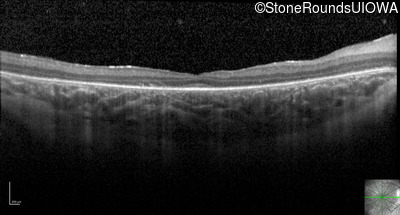

Optical Coherence Tomography - Right - 20/80 -1

Exemplar / OCT Stack